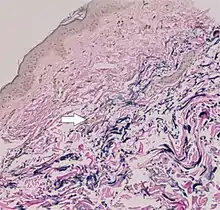

The diagnostic criteria for PXE are the typical skin biopsy appearance and the presence of angioid streaks in the retina. Criteria were established by consensus of clinicians and researchers at the 2010 biennial research meeting of the PXE Research Consortium.[29] and confirmed at the 2014 meeting[30] These consensus criteria state that definitive PXE is characterized by two pathogenic mutations in the ABCC6 or ocular findings – angioid streaks > 1 DD or peau d’orange in an individual <20 years of age together with skin findings:

- Diagnostic histopathological changes in lesional skin: Calcified elastic fibers in the mid and lower dermis, confirmed by positive calcium stain

| Pseudoxanthoma elasticum | LM: Mid-dermal calcification and fragmentation of elastic fibers EM: Mineralization in elastic fiber core |

| White fibrous papulosis of the neck | LM: Dermal fibrosis in papillary and mid-reticular dermis |

| Papular elastorrhexis | LM: Thickening of collagen bundles next to loss and fragmentation of elastic fibers |